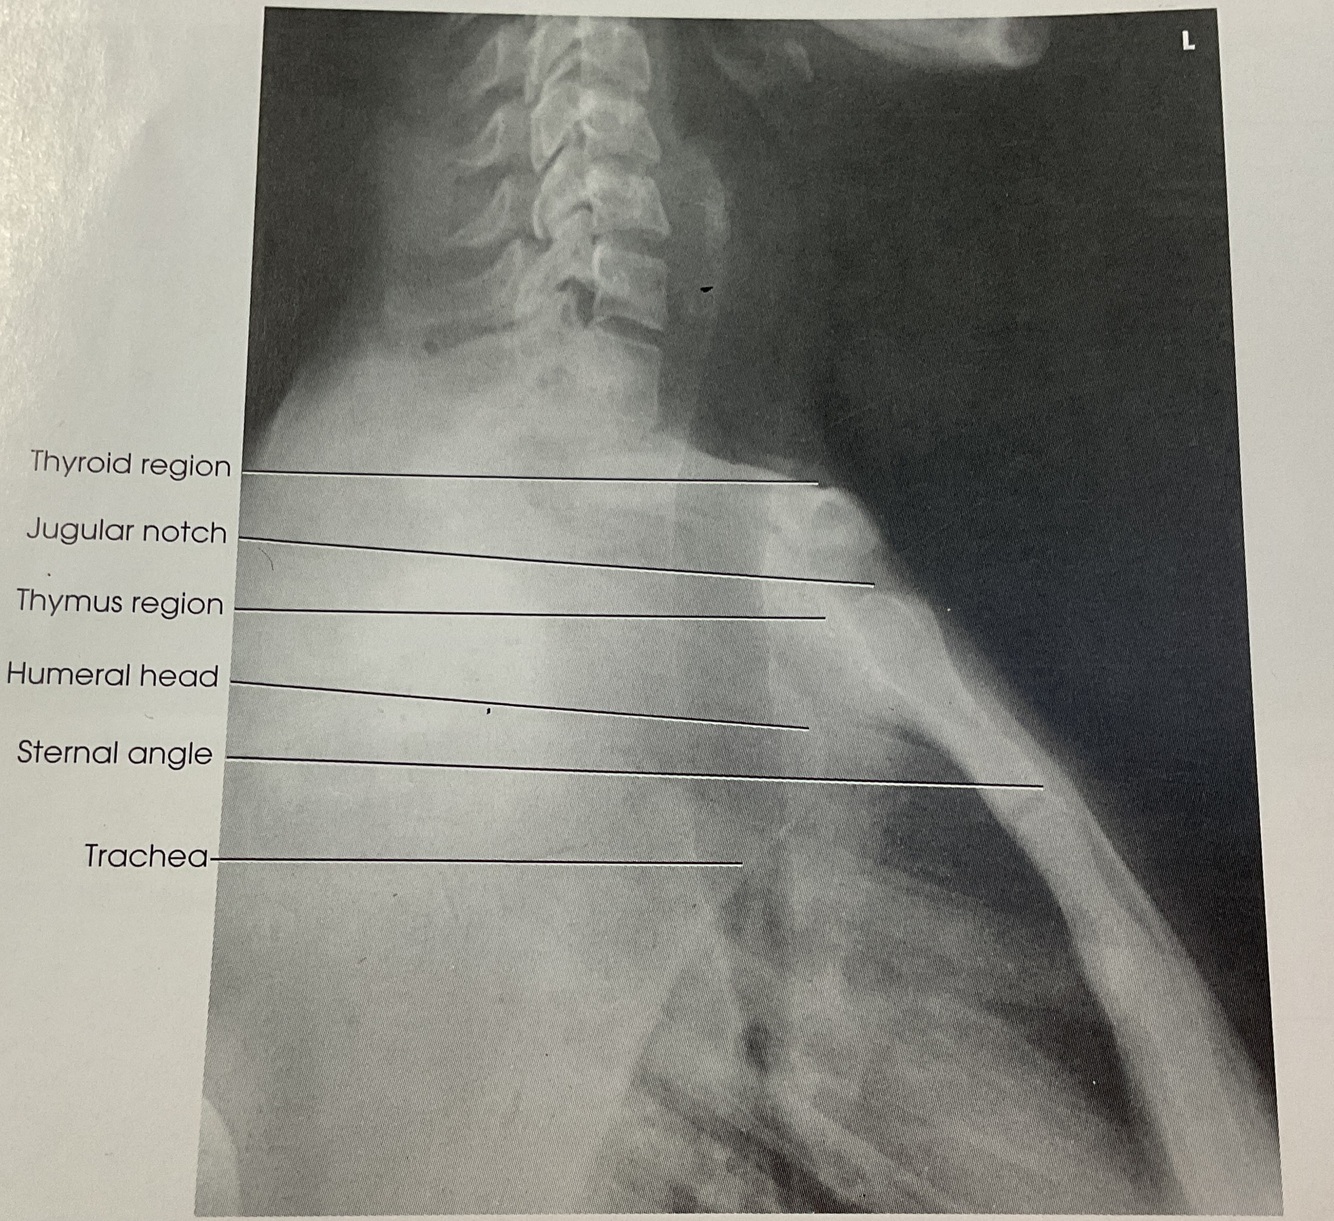

For: Trachea & Superior Mediastinum

@Lvl of Jugular Notch (point midway between Jugular Notch & Mid Coronal plane

Where do you center the IR for the Trachea & Superior Mediastinum? AP PROJECTION

A

Manubrium (Larynx & Sup Mediastinum)